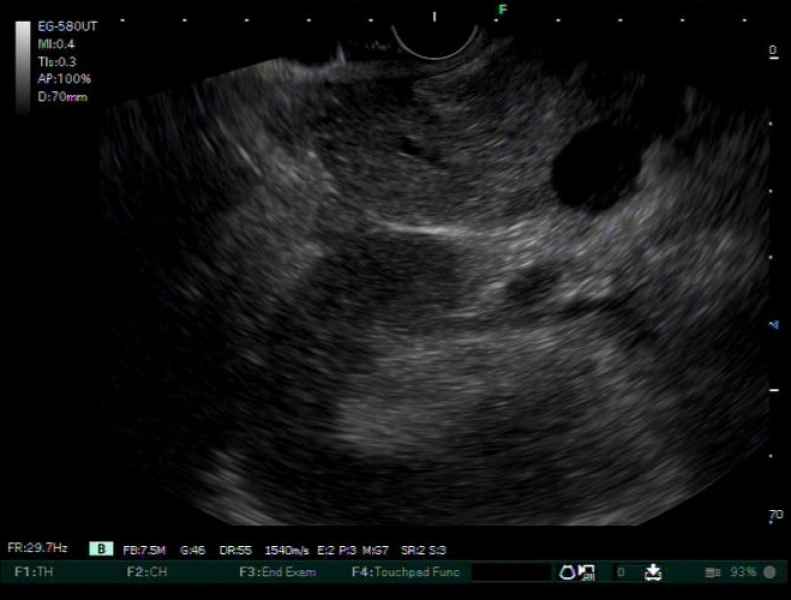

A case of pancreatic tuberculosis